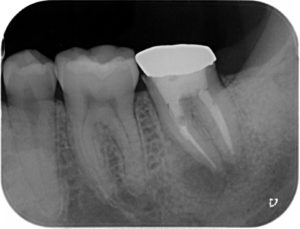

膿の症状、噛んだ時の症状、たたいた時の痛みなど、様々な項目をクリアした後は、根っこの中が綺麗になったと判断して、もう一度新しいお薬を詰めていきます。

根っこの治療終了後です。根っこの下にある黒い像は、この後ゆっくりとなくなっていきます。

いままで入っていなかった根っこの中にお薬が入ったのがわかるでしょうか??